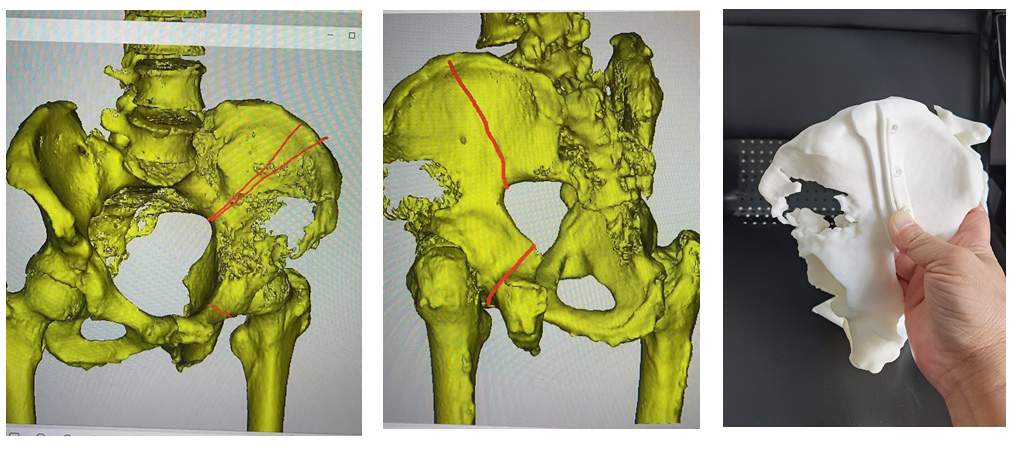

南医五院骨肿瘤规范化治疗团队与广东省人民医院骨肿瘤科团队组织讨论,为患者制定了术前3D打印个性化半骨盆假体及精准截骨导板(图2、3),术前介入栓塞骨肿瘤及周围的供血动脉围手术期准备下的骨盆切除髋关节功能重建手术。

图2:盆骨肿瘤切除范围及精准截骨导板

图3:定制3D打印个性化半骨盆置换髋假体

图4:3D打印截骨导板下精准切除骨盆肿瘤